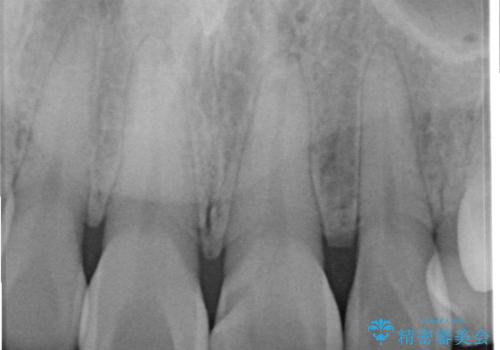

- 以前に前歯を折れた時、コンポジットレジンで修復したが、変色してきたことを主訴に来院されました。

今回は、セラミッククラウンによる修復を希望され、治療を行っています。

コンポジットレジンは、経年変化しやすい材料ですが、セラミックは変色しずらい材料となります。